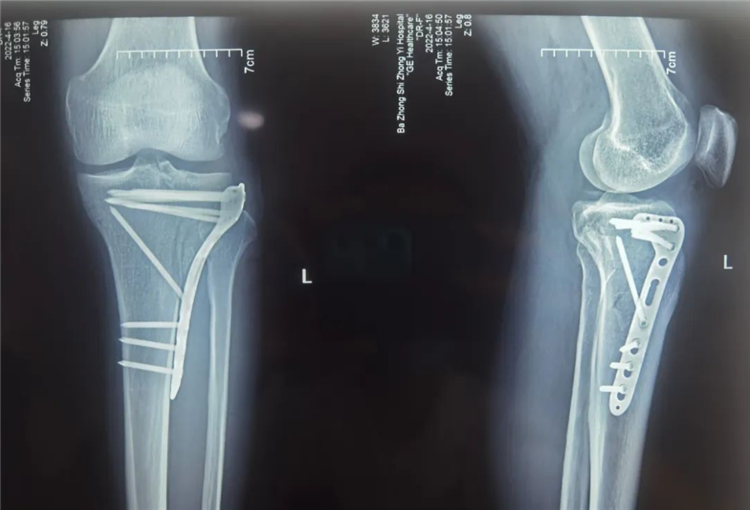

术中C臂透视见塌陷的平台高度恢复,骨折解剖复位

术后拍DR提示:骨折对位对线良好